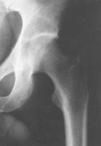

En los estudios radiológicos se observó osteoporosis difusa afectando a la cabeza, cuello y metáfisis femoral. En la gammagrafía con 99Tc apareció hipercaptación difusa y homogénea en cabeza y cuello femoral. La RM mostró disminución homogénea de la señal en T1 con aumento en T2 sugestivas de edema medular que afectaba cabeza, cuello y metáfisis femoral hasta la línea intertrocantérica, respetando en todo momento la articulación (Figs. 1 y 2). Las dos TAC mostraban alteraciones de la estructura y trabeculación ósea. La densitometría ósea mostró una densidad ósea de la cadera afecta del 81,8% frente a un 98% de la cadera contralateral respecto a la media observada para su sexo y edad. La analítica fue normal en todos los casos.

ABCDFigura 1. Estudios de imagen en un paciente varón de 40 años en el momento de la consulta. A: Rx AP de cadera que muestra marcada osteopenia afectando a cabeza, cuello y metáfisis femoral izquierda. B: Gammagrafía con 99Tc en la que se aprecia hipercaptación de la misma zona. C: Corte axial de RM con secuencia spin-eco potenciada en T1, donde se aprecia disminución de la señal en la cabeza femoral izquierda. D: Corte coronal de RM con eco de gradiente potenciada en T2 con aumento de la señal afectando a cabeza, cuello y metáfisis femoral izquierda.